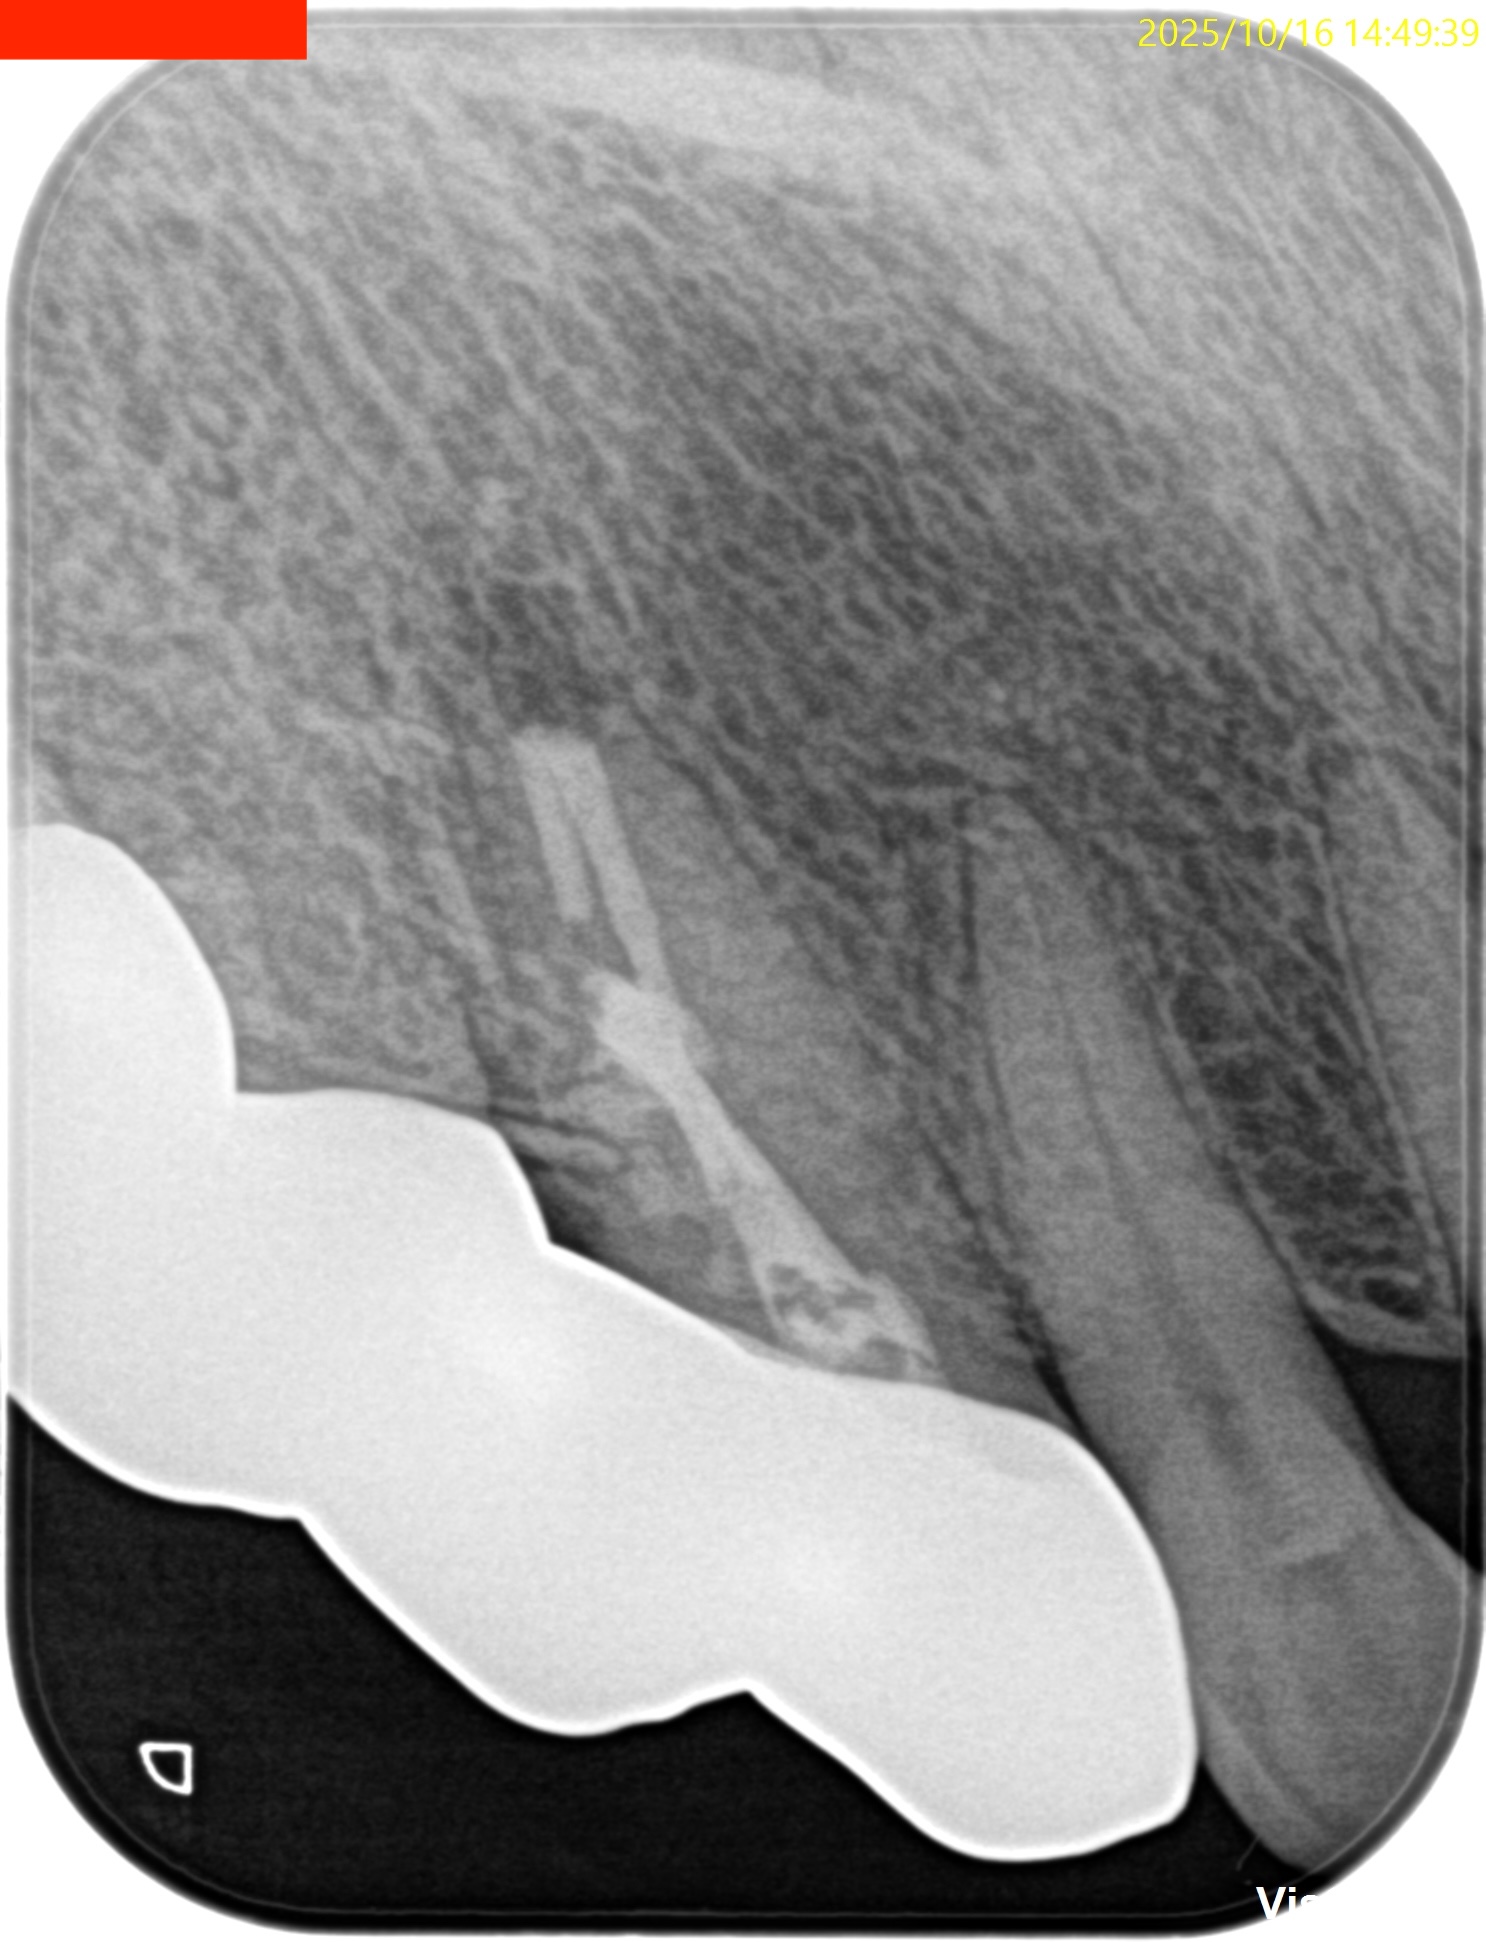

PA, CBCTを撮影した。

しょっぱい逆根管形成になったが主根管は確保されたので縫合して終了した。